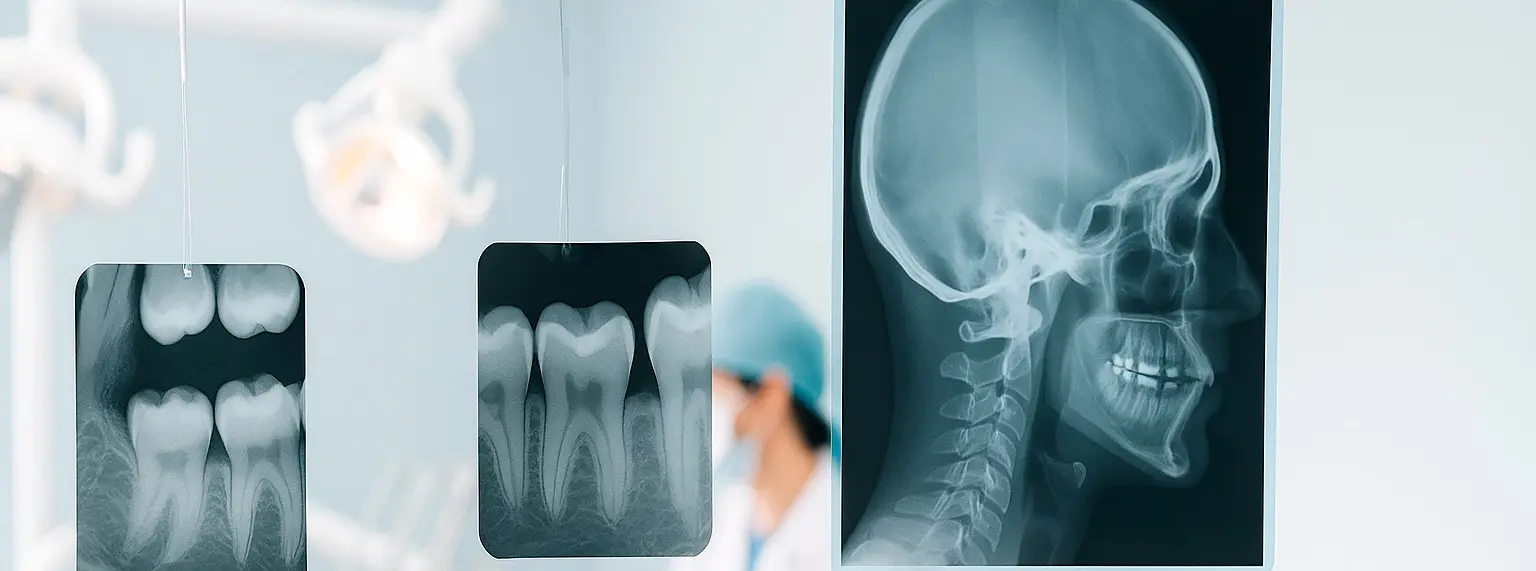

Cefalometrías dentales en San Miguel para análisis ortodóntico y planificación.

Los estudios cefalométricos utilizan la telerradiografía como base para realizar trazados y mediciones que apoyan la evaluación esquelética, dental y el seguimiento de tratamientos ortodónticos.

Un análisis cefalométrico es el trazado digital o manual de puntos anatómicos sobre una telerradiografía lateral, que permite medir ángulos, distancias y relaciones entre estructuras del cráneo, los maxilares y los dientes. A partir de esas medidas, el ortodoncista obtiene información objetiva sobre la base esquelética, el perfil dentario y el patrón facial del paciente.

Análisis cefalométrico sobre telerradiografía lateral en RX San Miguel

Trazado cefalométrico digital con puntos de referencia ortodóncicos.

Primero realizamos la telerradiografía lateral con cefalostato y distancia estándar, para minimizar magnificación y mantener la fidelidad de las medidas.